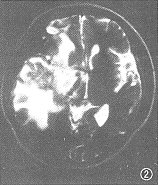

1.放射性脑坏死( radiation encephalic necrosis,REN):有4例5个病灶。右颞3个,左颞2个,1例为双侧。病灶在T1WI上呈大片不均匀低信号,T2WI上以高信号为主,中央有不规则等皮质信号区。注射Gd-DTPA后,病变区见明显强化灶,T2WI上的中央等信号区不强化,大小2.5 cm× 6.0 cm不等。其中4个完全或主要位于白质,1个累及灰质。病灶呈团块状,外形不规则呈粗大齿轮样。其中1 例手术病理提示该处为凝固性坏死。5 个病灶周围均见不同程度水肿,呈爪状沿白质蔓延;2个较重,波及同侧额顶及基底节区,占位效应显著;3 个较轻,只累及颞叶前中部,占位效应轻(图1~4)。

图1~4 为同一例患者。图1为T1WI,示右颞低信号灶,占位效应明显;图2为T2WI,示右颞额高信号灶,中部见等皮质T2信号区。图3,4示增强后病灶明显强化,内见非强化区,外观呈齿轮状,病灶主要累及白质